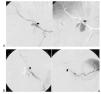

Once lesiones fueron roturas arteriales con formación de pseudoaneurisma de una arteria musculoesquelética (fig. 1) y 9 fueron lesiones en una arteria visceral (fig. 2), 4 de las cuales fueron lesiones de la arteria gastroduodenal (fig. 3), tres secundarias a complicaciones de una duodenopancreatectomía cefálica y otra a una punción directa con un catéter de drenaje 10 french de un absceso secundario a una colecistectomía.

Fig. 1. (A) (caso 13) Arteriografía selectiva de arteria glútea inferior izquierda que pone de manifiesto la rotura arterial y el punto de sangrado activo (flecha). (B) Arteriografía selectiva de glútea inferior e imagen simple sin sustracción que muestran el molde de Onyx cerrando selectivamente el punto sangrante, permaneciendo permeables el resto de ramas arteriales (flecha).